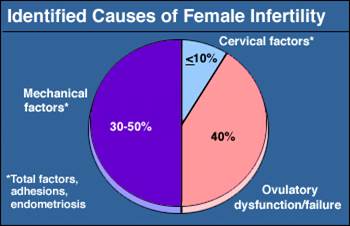

We are conducting research to investigate if a manual therapy protocol that many physical therapists utilize today is an effective treatment for mechanical infertility. This technique is not well known because of limited clinician training and limited anecdotal research to validate its use. Read the case series where 6/10 women conceived with an average of 4 PT sessions.

-1 in 8 couples will struggle with infertility during their reproductive years.

-Current infertility treatment is expensive and comes with moderate health risks.

-We believe low cost options for mechanical infertility should be available to all women across the globe.